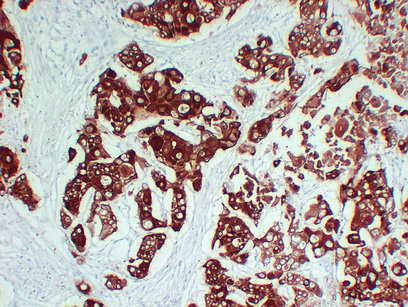

Immunohistochemistry analysis of paraffin-embedded Lung squamous cell carcinoma using Cytokeratin 6A antibody. High-pressure and temperature Sodium Citrate pH 6.0 was used for antigen retrieval.